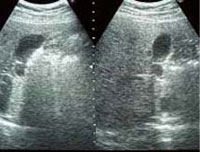

胃内視鏡(胃カメラ)

食道・胃・十二指腸の診断を行います。

当院では、従来のものより痛みや苦痛の少ない極細内視鏡を使用しています。